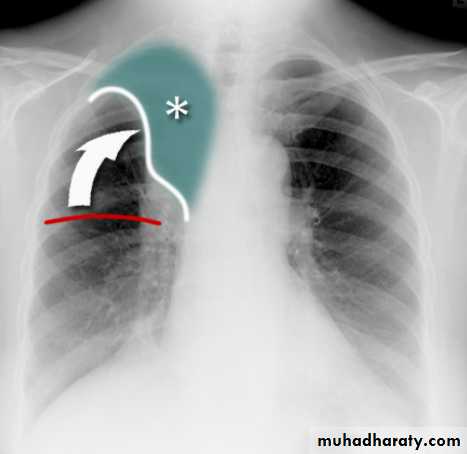

Right upper lobe collapse has distinctive features, and is usually easily identified on frontal chest radiographs .

Radiographic features

Chest radiograph

Collapse of the right upper lobe is usually relatively easy to identify on frontal radiographs. Features consist of :

increased density in the upper medial aspect of the right hemithorax

elevation of the horizontal fissure

loss of the normal right medial cardiomediastinal contour

elevation of the right hilum

hyperinflation of the right middle and lower lobe result in increased translucency of the mid and lower parts of the right lung

right juxtaphrenic peak

A common cause of lobar collapse is a hilar mass. When a right hilar mass is combined with collapse of the right upper lobe, the result is an S shape to elevated horizontal fissure. This is known as Golden S sign .

Non-specific signs indicating right sided atelectasis are also usually present including:

elevation of the hemidiaphragm

crowding of the right sided ribs

shift of the mediastinum and trachea to the right